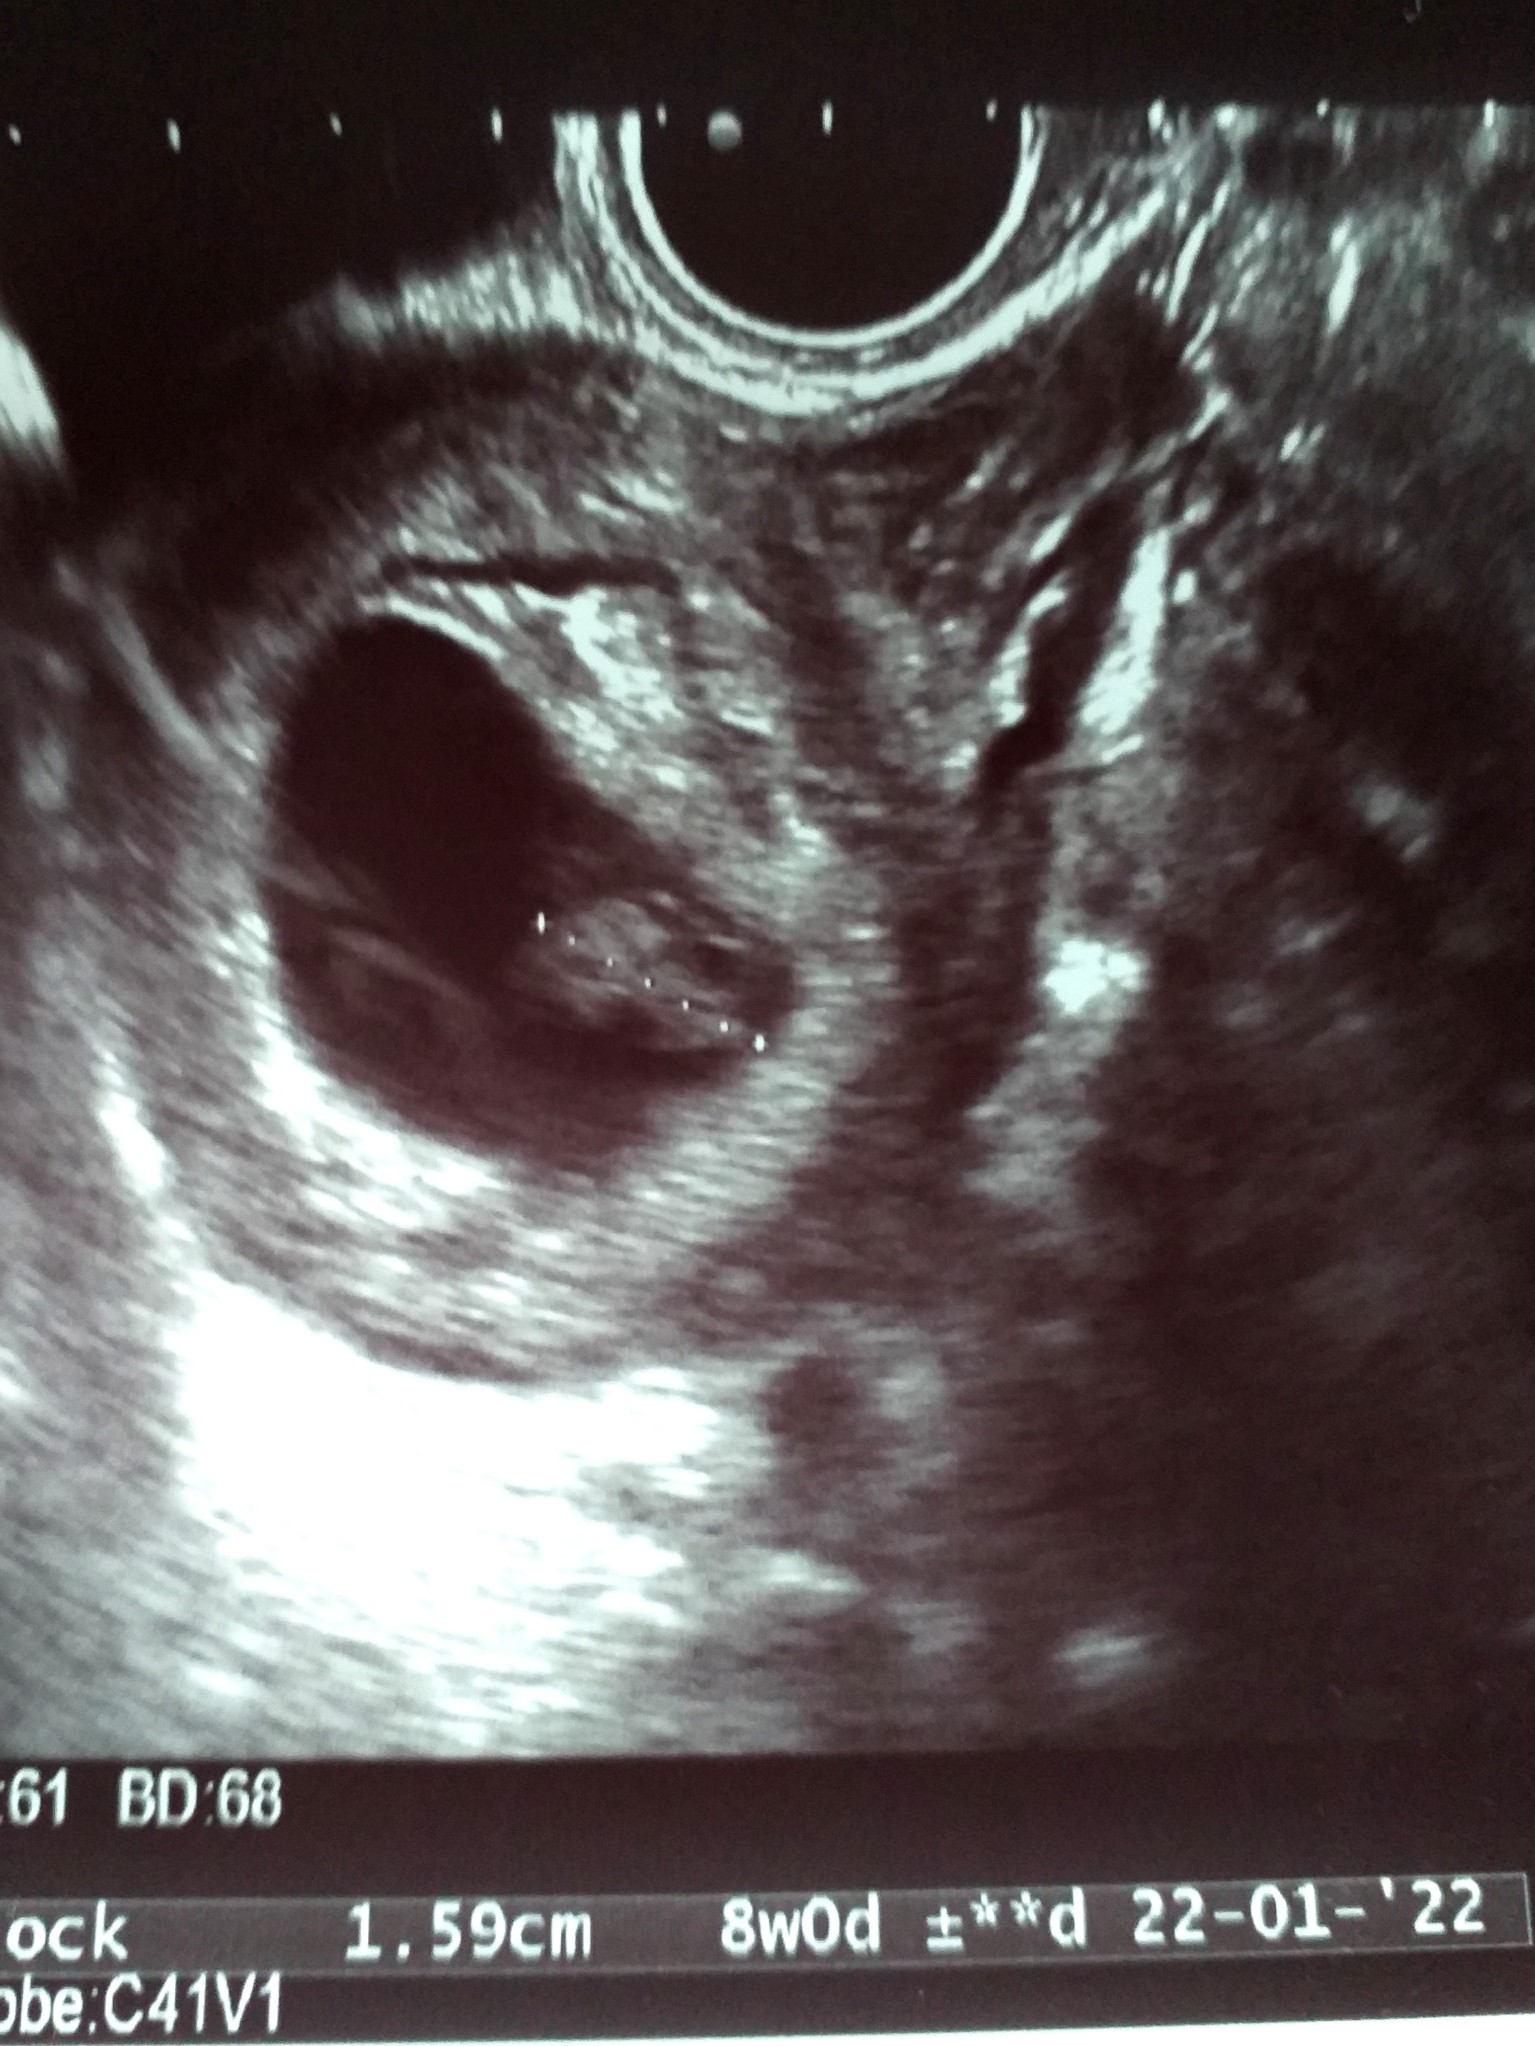

Przepraszam że namieszalam z tą tajną gupą a sama przy trójce czasem znikam na dłużej. Byłam dzisiaj na badaniu. Wszystko dobrze. 8 tydz i 2 dni. Ale zdjęcia słabe, też chciałam mieć takiego "miśka haribo" a nic prawie nie widać. Tyle kasy bo musialam iść prywatnie a miśka nie widać. Na ekranie nawet był ale nie uchwyciła.